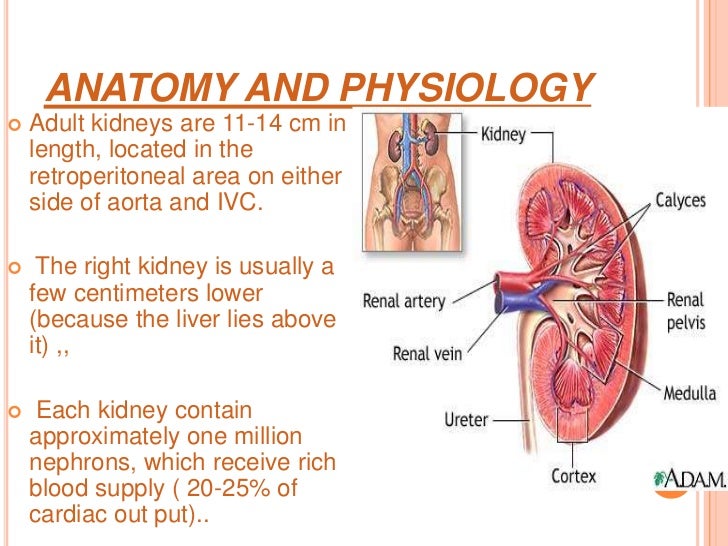

The kidneys are 11 centimeters long paired reddish brown organs situated on the posterior wall of the abdominal cavity one on each side of the vertebral column and capped by the adrenal gland. H ions are produced as a natural byproduct of the metabolism of dietary proteins and accumulate in the blood over time. Connective tissue anchors the kidneys to surrounding structures and helps maintain their normal position.

Due to the presence of the liver the right kidney is slightly lower than the left kidney. They are about 1114 cm in length 6 cm wide and 4 cm thick and are directly covered by a fibrous capsule composed of dense. Anatomy of the urinary system.

The kidneys monitor and regulate the levels of hydrogen ions h and bicarbonate ions in the blood to control blood ph. Glomerular filtration glomerular filtration is the renal process whereby fluid in the blood is filtered across the capillaries of the glomerulus. The right kidney is lower than the left due to displacement by the liver.

Location of the kidneys there are two kidneys which lie retroperioneally in the lumbar area. The angiotensinconverting enzyme converts angiotensin i to angiotensin ii which stimulates the adrenal cortex to secrete aldosterone a hormone that is involved in increasing blood pressure. The basic anatomy and physiology of the kidney how kidney function changes through life the anatomy of the kidney the kidneys are comple x and beautiful organs.